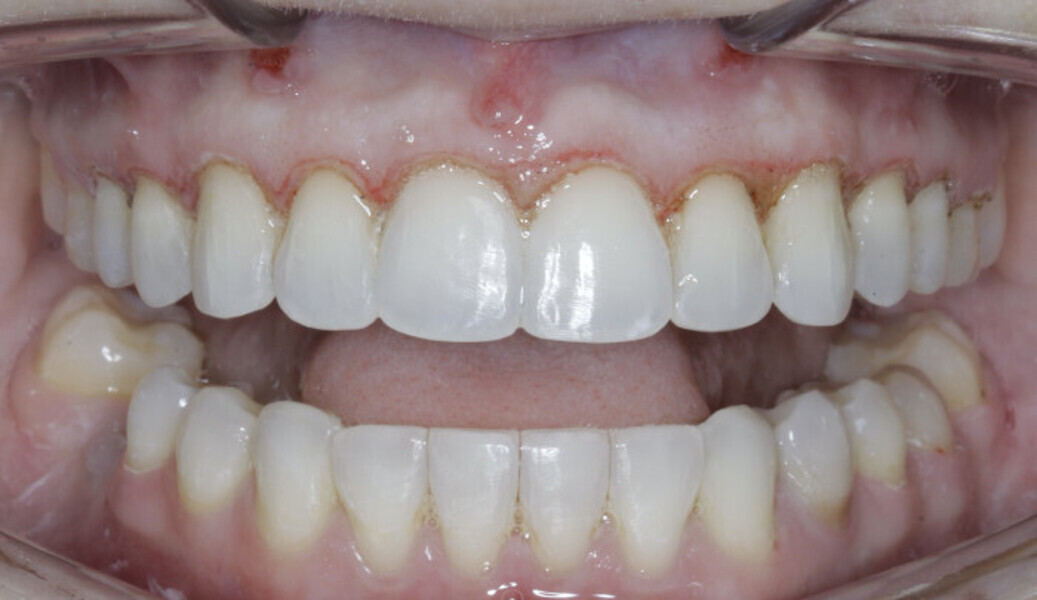

New Age orthodontics and orthopaedics with temporary anchorage devices